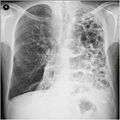

A chest X-ray and complete blood count may be useful to exclude other conditions at the time of diagnosis.[61] Characteristic signs on X-ray are overexpanded lungs, a flattened diaphragm, increased retrosternal airspace, and bullae while it can help exclude other lung diseases, such as pneumonia, pulmonary edema or a pneumothorax.[62] A high-resolution computed tomography scan of the chest may show the distribution of emphysema throughout the lungs and can also be useful to exclude other lung diseases.[15] Unless surgery is planned, however, this rarely affects management.[15] An analysis of arterial blood is used to determine the need for oxygen; this is recommended in those with an FEV1 less than 35% predicted, those with a peripheral oxygen saturation of less than 92% and those with symptoms of congestive heart failure.[14] In areas of the world where alpha-1 antitrypsin deficiency is common, people with COPD (particularly those below the age of 45 and with emphysema affecting the lower parts of the lungs) should be considered for testing.[14]

Chest X-ray demonstrating severe COPD. Note the small heart size in comparison to the lungs.